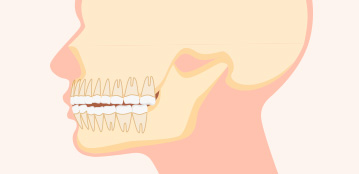

양악 돌출

치아 각도는 정상이나

치아를 감싼 턱뼈가

앞으로 튀어나온 경우